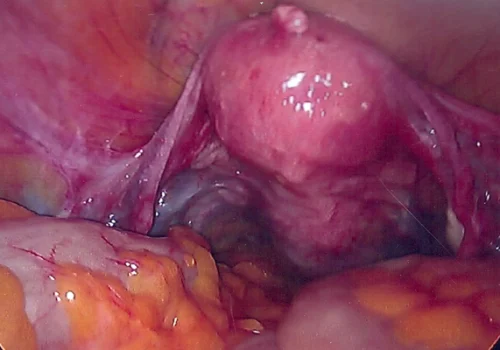

Procedure

She subsequently underwent Total Laparoscopic Hysterectomy and removal of both Tubes and Ovaries.